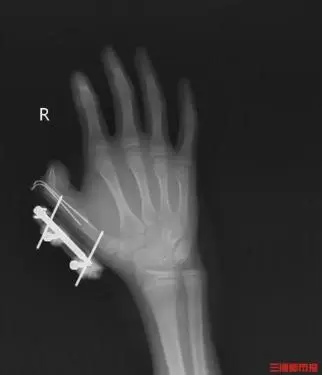

5.若被干冰冻伤或炸伤应立即就医。